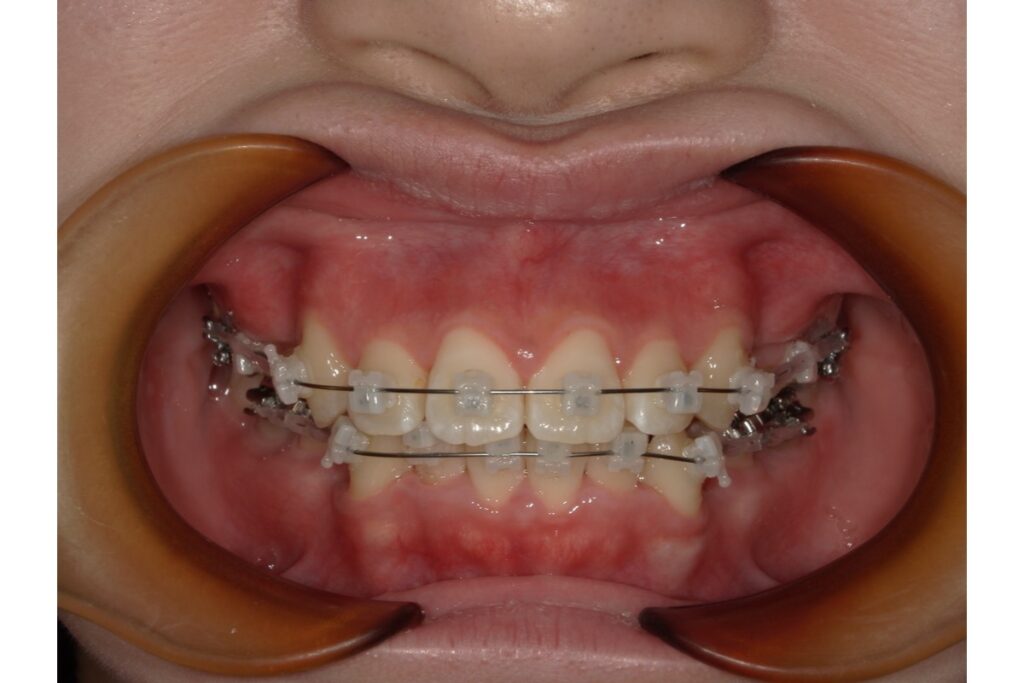

現在では金属を使わない矯正器具も増えてきています。例えば、セラミックのブラケットや透明のワイヤー。これらは金属を使用していないため、アレルギー反応もそうですが審美性にも配慮した治療が可能になります。

写真のブラケットが金属を使用していないブラケットです↑